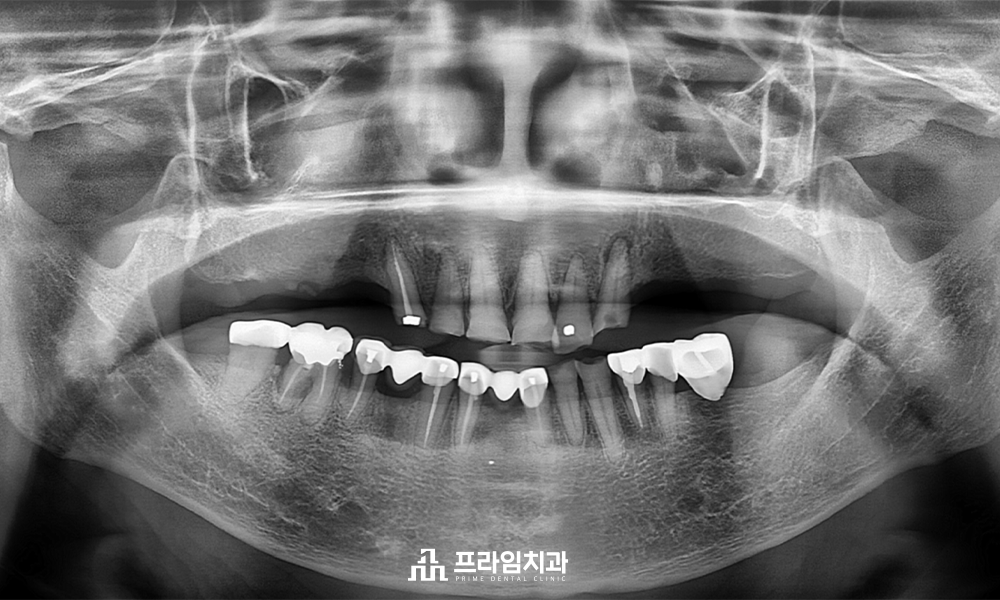

위 환.자분은 88세 여성분으로

전주에 혼자 거주하고 계시는 분이신데요.

치과 공포증으로 인해 여태까지

치료를 미루고 계셨다고 하셨습니다.

윗니가 앞니 6개만 남아 있는 채로

10년 넘게 앞니로만 식사를 하고 계신 상태로

경제적인 여유가 충분하나 임플란트 수술이 무서워

치료를 포기하고 계시다가 큰마음 먹고

임플란트를 하기로 결정하고 난 후

자제분이 계신 서울의 치과 몇 군데에서

상담을 받으시고 오셨다고 하셨습니다.

그러던 중 저희 치과에 내원해 주셨고

무절개임플란트에 관한 설명을 들으시고

타치과에서는 잇몸뼈 이식을 해야 한다고

설명 들으셨지만 잇몸뼈 이식 없는

매직 코어를 이용한 본.원의 편안한 임플란트

설명을 들으시고 진행하기로 하였습니다.